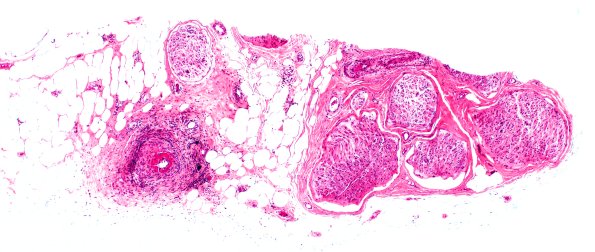

Washington University Experience | PERIPHERAL NEUROPATHY | 11 VASCULITIS - VASCULOPATHY | 4 Polyarteritis nodosa | 12A1 PAN (Case 12) H&E 4X 1

Case 12 History ---- The patient is a 76 year old woman with peripheral neuropathy. Operative procedure: Right sural nerve biopsy. ---- 12A1,2 Fibrinoid necrosis of the sural nerve in this case. (H&E)